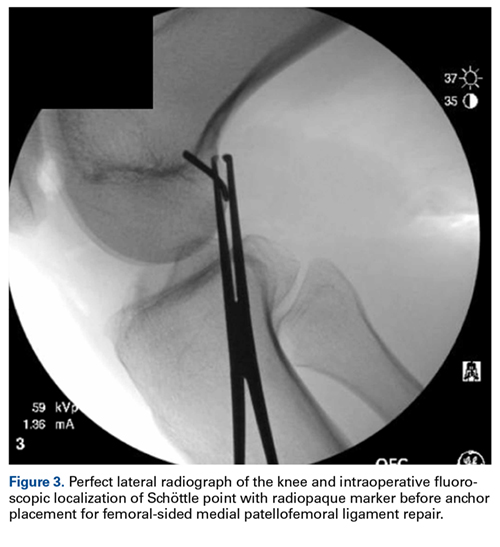

Although large osteochondral lesions may be visible on plain radiographs, MRI can be considered because of the relatively high incidence of osteochondral lesions in this population.21 In addition, MRI best determines the location and the extent of MPFL injury when early surgical intervention is being considered after discussion with the patient, or in cases of a concomitant osteochondral lesion.20 MPFL repair is best indicated in a young patient with a first-time patellar dislocation and a patella- or femoral-based bony avulsion or isolated patella- or femoral-based rupture (Figure 2). However, in a patient with a multifocal intrasubstance ligamentous injury, and in a high-level athlete being considered for surgery, MPFL reconstruction may provide more reliable outcomes.11,29Numerous open and arthroscopic MPFL repair techniques have been described.10,30-33 Nevertheless, comparative studies are limited, and the greatest debate about MPFL repair continues to be appropriate indications. Arthroscopic MPFL repair can be technically demanding and can fully visualize only patella-based injuries. In addition, all-arthroscopic repair techniques may place suture material in the joint, which causes concern regarding suture irritation. As a result, the majority of MPFL repair techniques described in the literature use an open approach, which typically includes a 4-cm to 5-cm longitudinal incision along the medial aspect of the patella. Sharp dissection is carried down through the medial retinaculum to the underlying joint capsule. The plane between the medial retinaculum and the underlying joint capsule is bluntly developed posteriorly until the medial epicondyle and the adductor tubercle are palpated. For a patella-based rupture, the MPFL is defined within layer 2, and 2 suture anchors are placed within the superior third of the patella. Although there are other patellar fixation methods, suture anchors provide adequate fixation with minimal risk of iatrogenic patellar fracture. With anchors in place, horizontal mattress sutures are placed in the stump of the MPFL. For femoral-based ruptures, the same surgical exposure is used to identify the MPFL. However, depending on the size of the incision and the mobility of the tissue, a second incision can be made posterior and parallel to the first—best achieved using a spinal needle to fluoroscopically localize Schöttle’s point.16 An incision is made in line with the spinal needle, and dissection is continued down to the previously developed extracapsular plane. Under fluoroscopic guidance (Figure 3), 1 or 2 suture anchors are placed at Schöttle point, and horizontal mattress sutures are placed through the avulsed MPFL femoral origin.